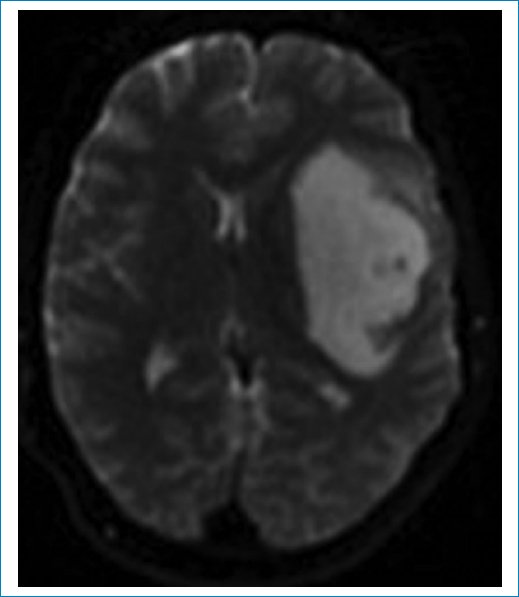

Las imágenes de resonancia magnética (RM) muestran una masa frontoinsular izquierda, hipointensa en la secuencia ponderada en T1 (Fig. 1), hiperintensa en T2 (Fig. 2) e hiperintensa en FLAIR (Fig. 3), pero con centro de menor intensidad. Este hallazgo, llamado “signo de la discrepancia”, es propio de las neoplasias gliales con IDH (isocitrate dehidrogenase) mutado y sin codeleción en 1p/19q1,2, y se observa en los astrocitomas. La codeleción 1p/19q es propia de los oligodendrogliomas3,4. La volumetría indica un volumen de 84 cm3 (Fig. 4).

Figura 2. Secuencia ponderada en T2. Masa hiperintensa.

Figura 3. Secuencia FLAIR. Hiperintensidad mayor en la periferia (“signo de la discrepancia”), típica de los gliomas, IDHm sin codeleción 1p/19q.